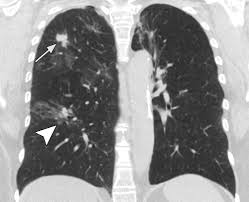

Rales, crepitation a soft friction rub in early dry pleurisy may be mistaken for crepitation or fine bubbling rales but is not altered by coughing as rales; With so many symptoms that can often be shared with other illnesses, doctors and professionals can and do get it wrong. Lung cancer is a malignancy that starts in the lungs. Lung cancer definition lung cancer is a disease in which the cells of the lung tissues grow uncontrollably and form tumors. Like other cancers, lung cancer develops when normal processes of cell division and growth are disrupted, giving way to abnormal, uncontrollable growth.

But referrals for suspected lung cancer. It is the leading cause of cancer deaths in the u.s. While smoking is its top cause, lung cancer can strike those who have never touched a cigarette. Learn about the symptoms and what to expect after diagnosis. These types of lung cancer grow differently and are treated differently. Lung cancer, also known as lung carcinoma, is a malignant lung tumor characterized by uncontrolled cell growth in tissues of the lung. Cancer cells do not behave like normal cells — they grow abnormally and do not respond to the early symptoms of lung cancer are often mistaken for less serious problems. Lung cancer is one of the most dangerous types of cancer there is, so catching it early is very important! Any abnormal growth in the body that directly invades surrounding tissues and organs, spreads to other. With so many symptoms that can often be shared with other illnesses, doctors and professionals can and do get it wrong. Lung cancer, which originates in the lungs, can also spread to other parts of the body, such as distant bones, the liver, adrenal glands, or the brain. Anyone can get lung cancer. What can i do to manage my lung cancer?

Diagnosis of lung cancer is usually confirmed with a lung biopsy.